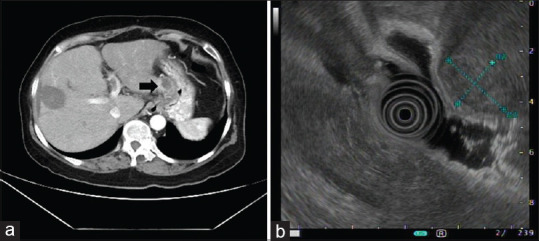

Unusual upper gastrointestinal bleeding following radiofrequency ablation and transarterial chemoembolization for hepatocellular carcinoma.

肝细胞癌射频消融和经动脉化疗栓塞后不寻常的上消化道出血。